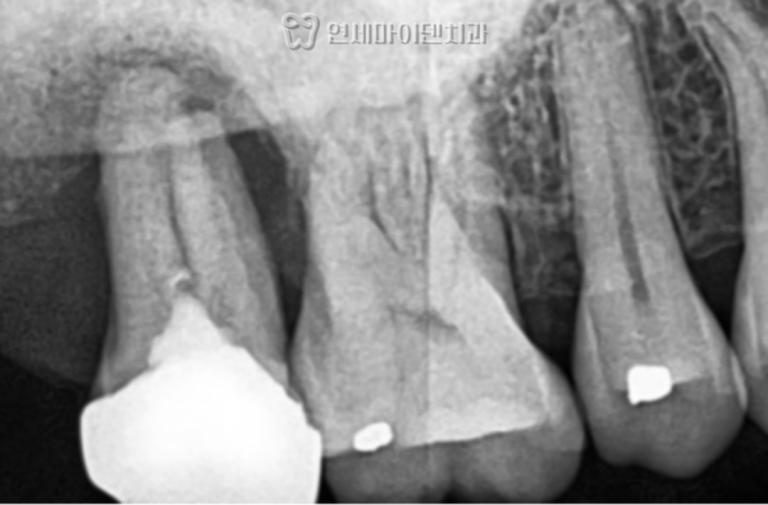

엑스레이 검사 결과, 해당 치아의 뿌리 주변 치조골이

심하게 흡수된 상태로 확인되었습니다.

겉보기에는 일부 뿌리가 정상처럼 보였으나,

세균막이 깊이 침투하여 치근 주위의 골소실이

광범위하게 진행된 상태였습니다.

CT 촬영 결과, 치아 후방부의 뼈는 완전히 흡수되어 있었지만

전방부에는 일부 치조골이 남아 있어서

고정력을 확보할 수 있었습니다.